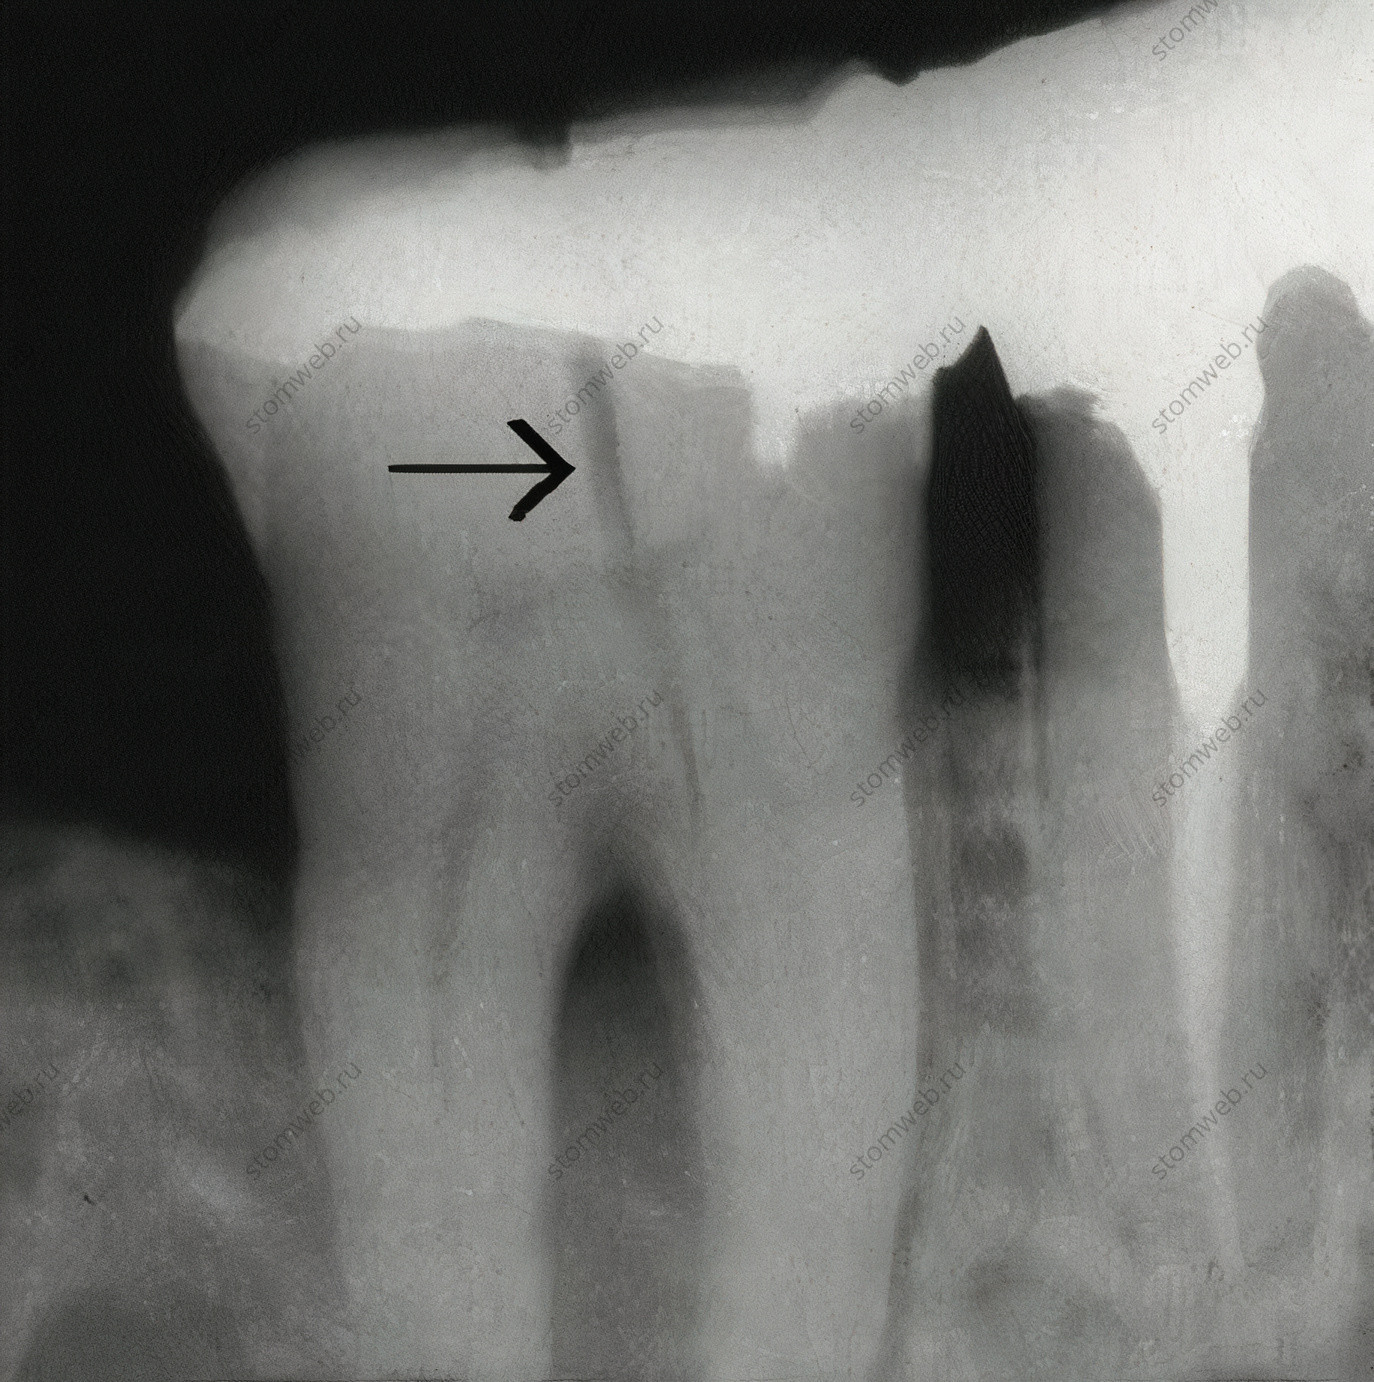

Принято, что рентгенологическое исследование, хоть и критично важно для других случаев, редко информативно при подозрениях на трещины. Это из-за того, что линия перелома в большинстве случаев проходит в мезиодистальном направлении, и рентгеновский луч проходит перпендикулярно линии перелома. Однако, если перелом проходит в букколингвальном направлении, на снимке будет четко видна линия трещины (Рис. 17)

Рисунок 17. Рентгенограмма нижнечелюстного моляра с показанной трещиной (стрелка) в букко-лингвальном направлении. Поскольку рентгеновский луч проходит параллельно трещине, ее видно на снимке.